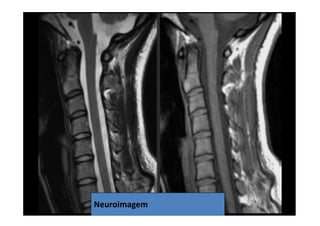

• 3. Ressonância Magnética

Opção preferencial para detecção de

patologias de partes moles tais como hérnia

de disco e tumores. Estudo realizado em 100

pacientes com doenças na laringe, sem

queixas clínicas relacionados à coluna cervical,

evidenciaram 20% de lesão discal em

pacientes entre 45-54 anos e 57% com mais de

64 anos.

07/12/2015 Dr. José Heitor M. Fernandes 76Neuroimagem